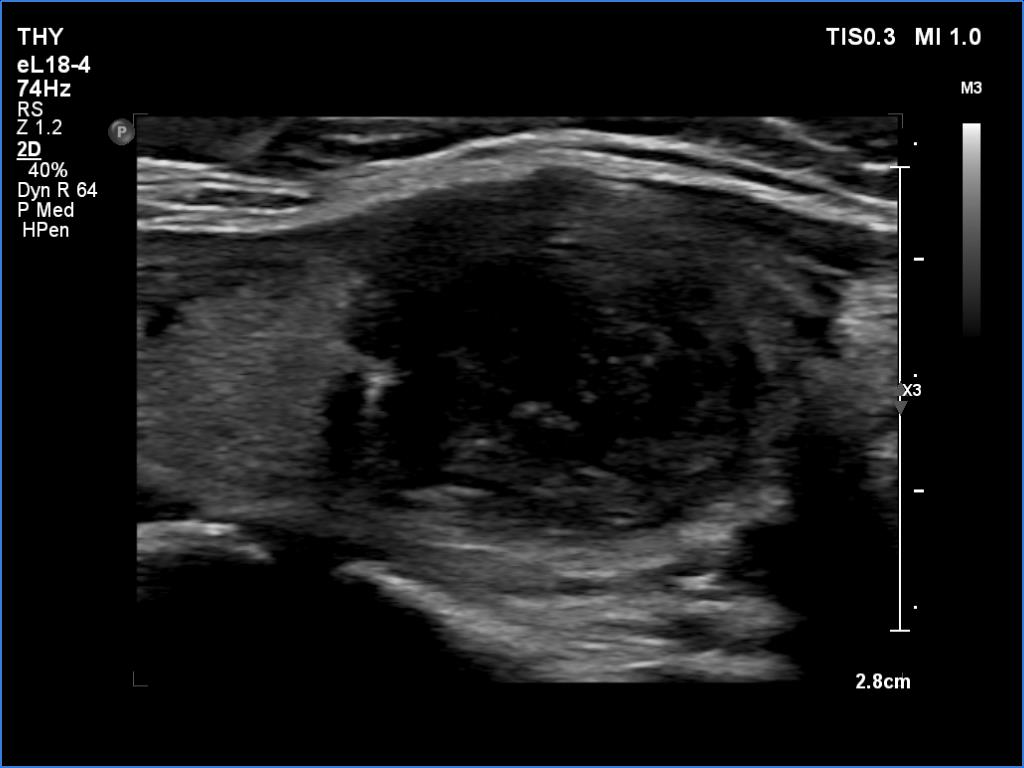

Ultrasonography revealed an echonormal thyroid. There was dominantly moderately hypoechoic nodule in the right lobe. Some parts of the lesion were deeply hypoechoic, and a few small cystic chambers were also within. The nodule presented with irregular shape and borders and had intranodular echogenic figures, primarily granules.

It is ambiguous how to interpret the echogenic figures. Although the presence of irregular shape and borders increases the likelihood that the echogenic granules are indeed microcalcifications, comet-tail artifacts must be also considered.

It is worth comparing the images recorded by using different settings. By using harmonization, we lose the details of very hypoechoic areas. Essentially, the latter seem to be anechoic.